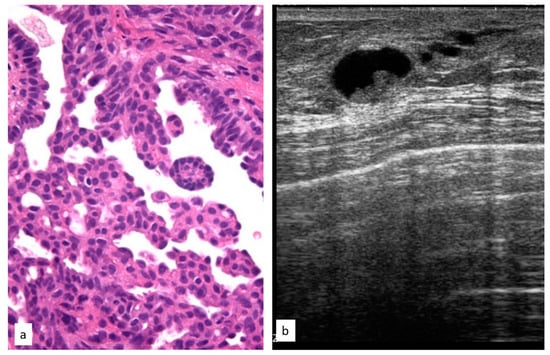

The initial radiological findings were two microcalcifications, 90 masses, and one architectural distortion; the mean radiological suspicion level was BIRADS 4 (range 2–5). Illustrative radiologic and histologic examples of atypical papillary lesions are shown in Figure 6.

Figure 6.

Histologic picture (a, Magnification (×20)) and ultrasound presentation (b) of atypical papillary lesions.

Of the 93 PL patients, 9 (9.7%) developed subsequent breast cancer during follow-up after a median time interval of 51.1 months; in 7 (77.7%) cases the new cancer was in the same breast as the PL and in 2 (22.2%) cases the cancer was found in the contralateral breast.